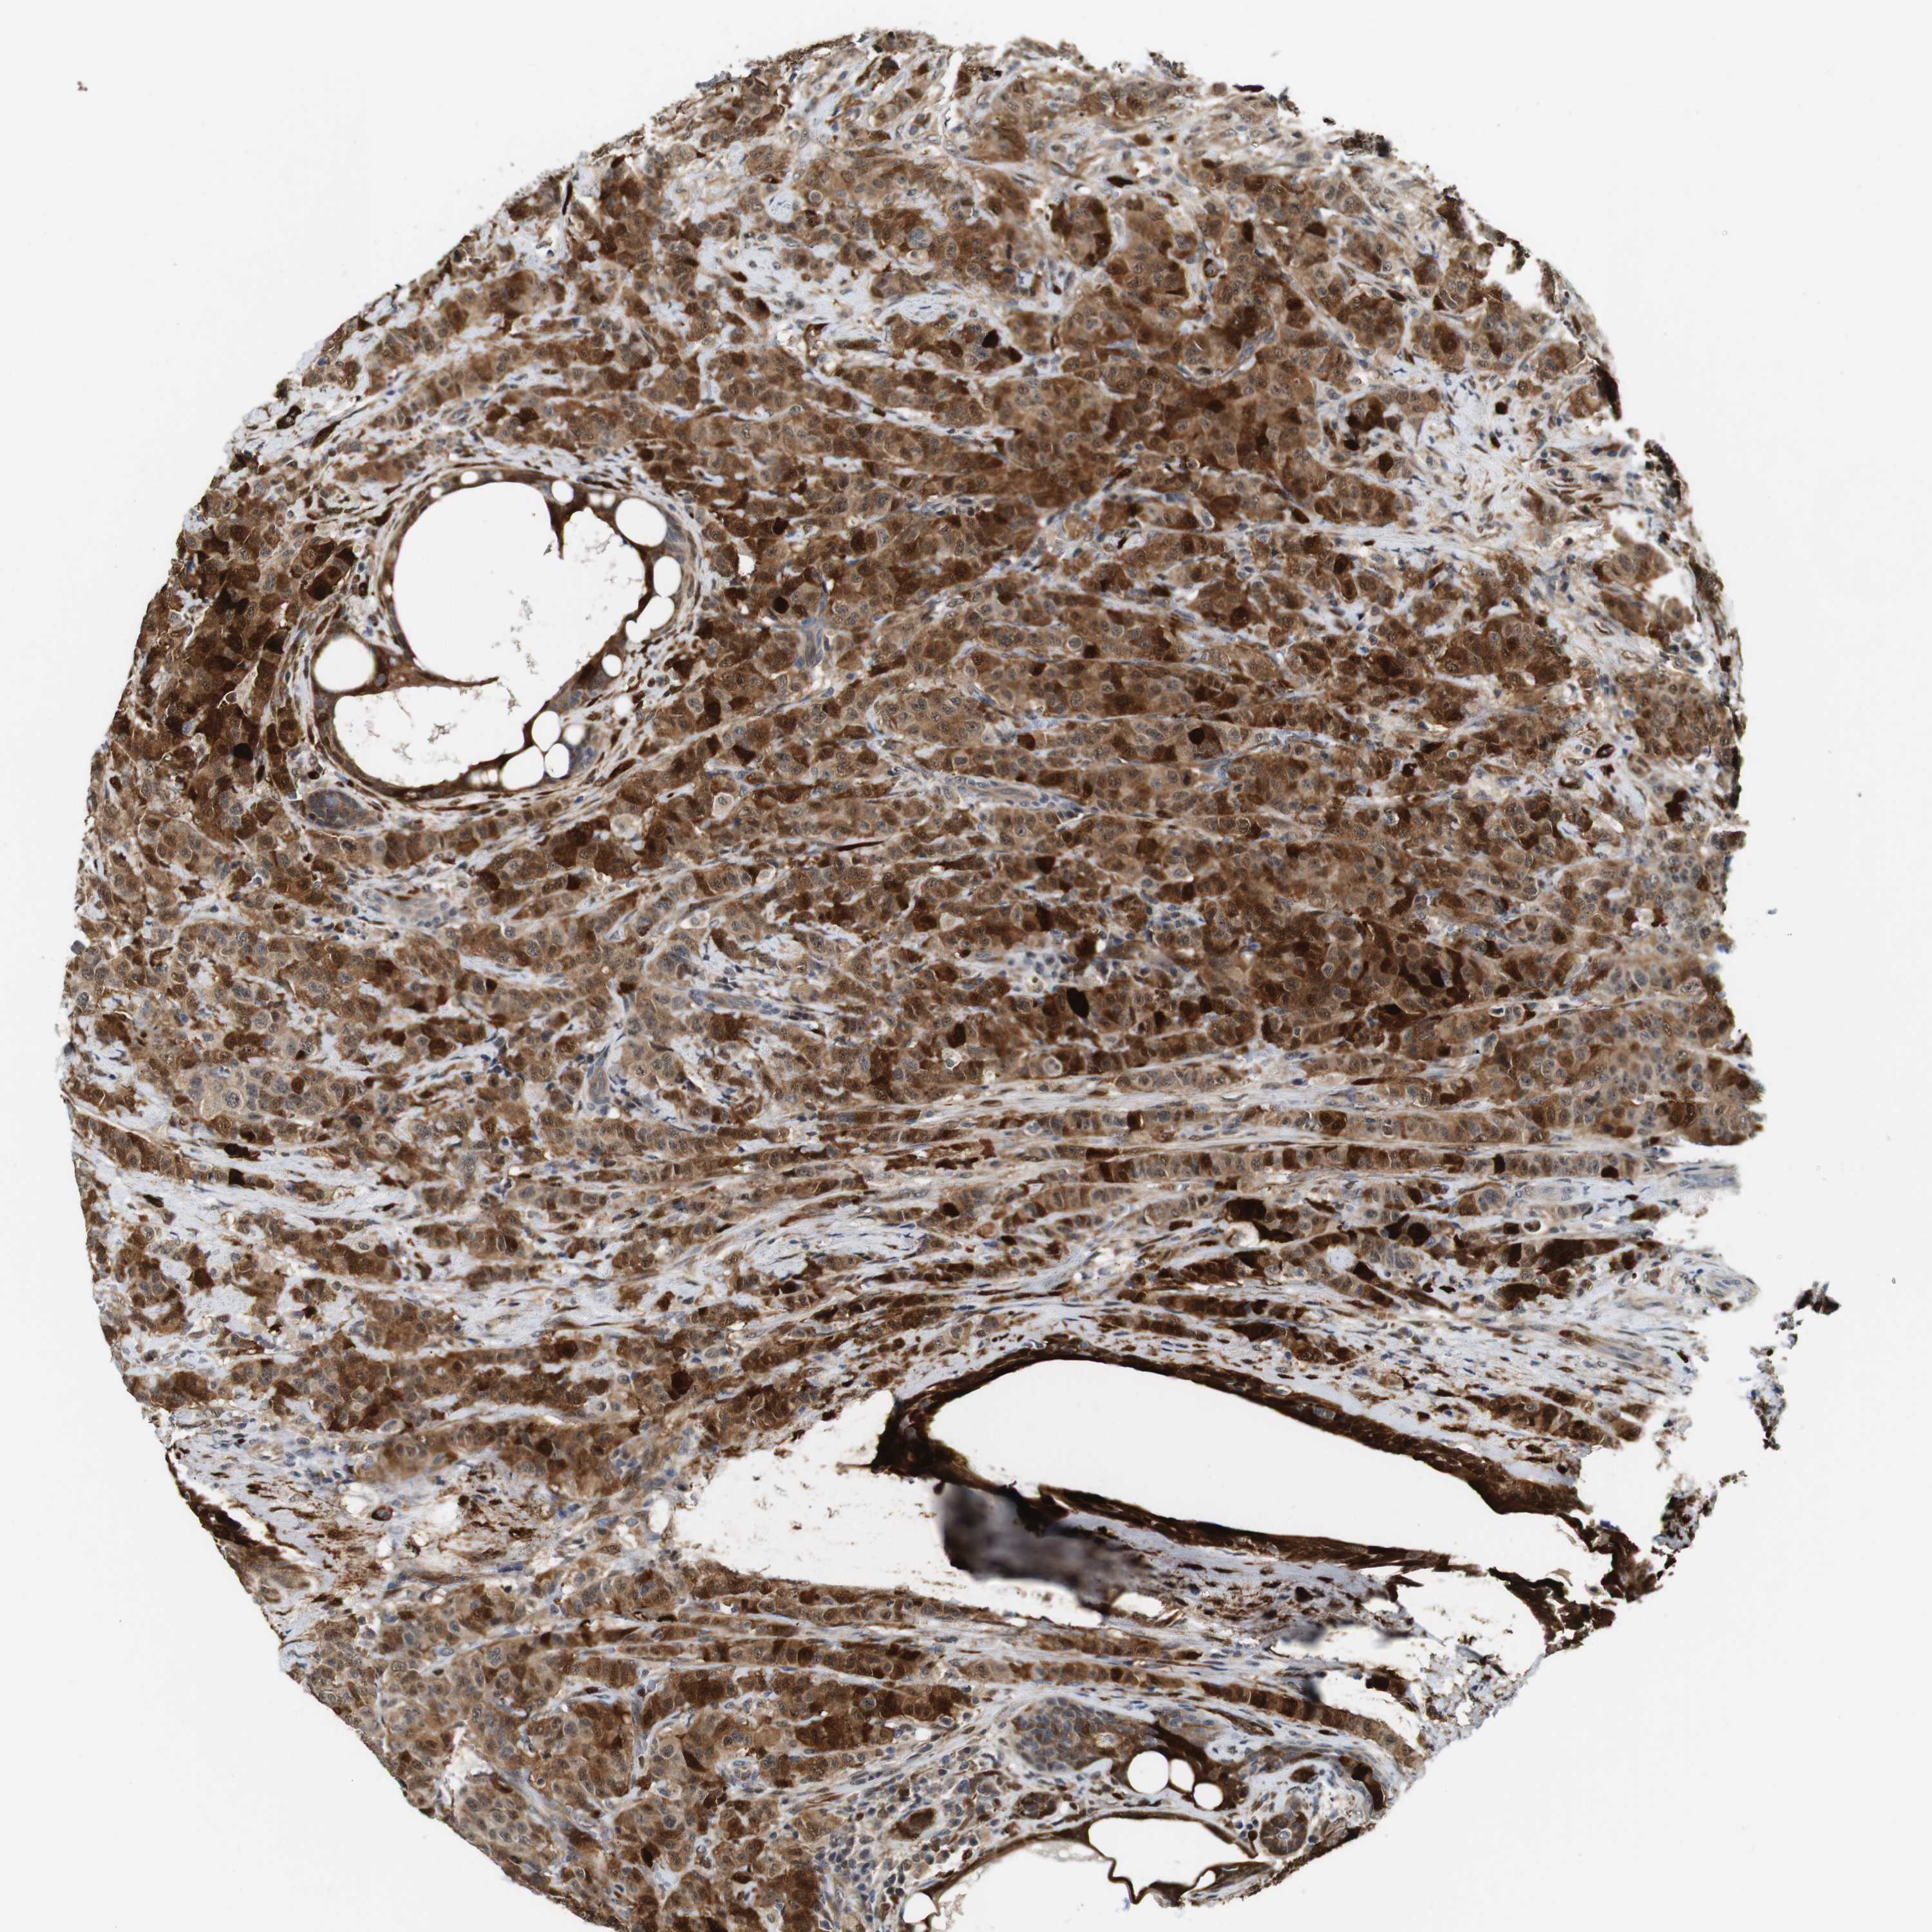

CANCER BREAST CANCER Show tissue menu

BRCA TCGA BRCA VALIDATION PROTEIN EXPRESSION